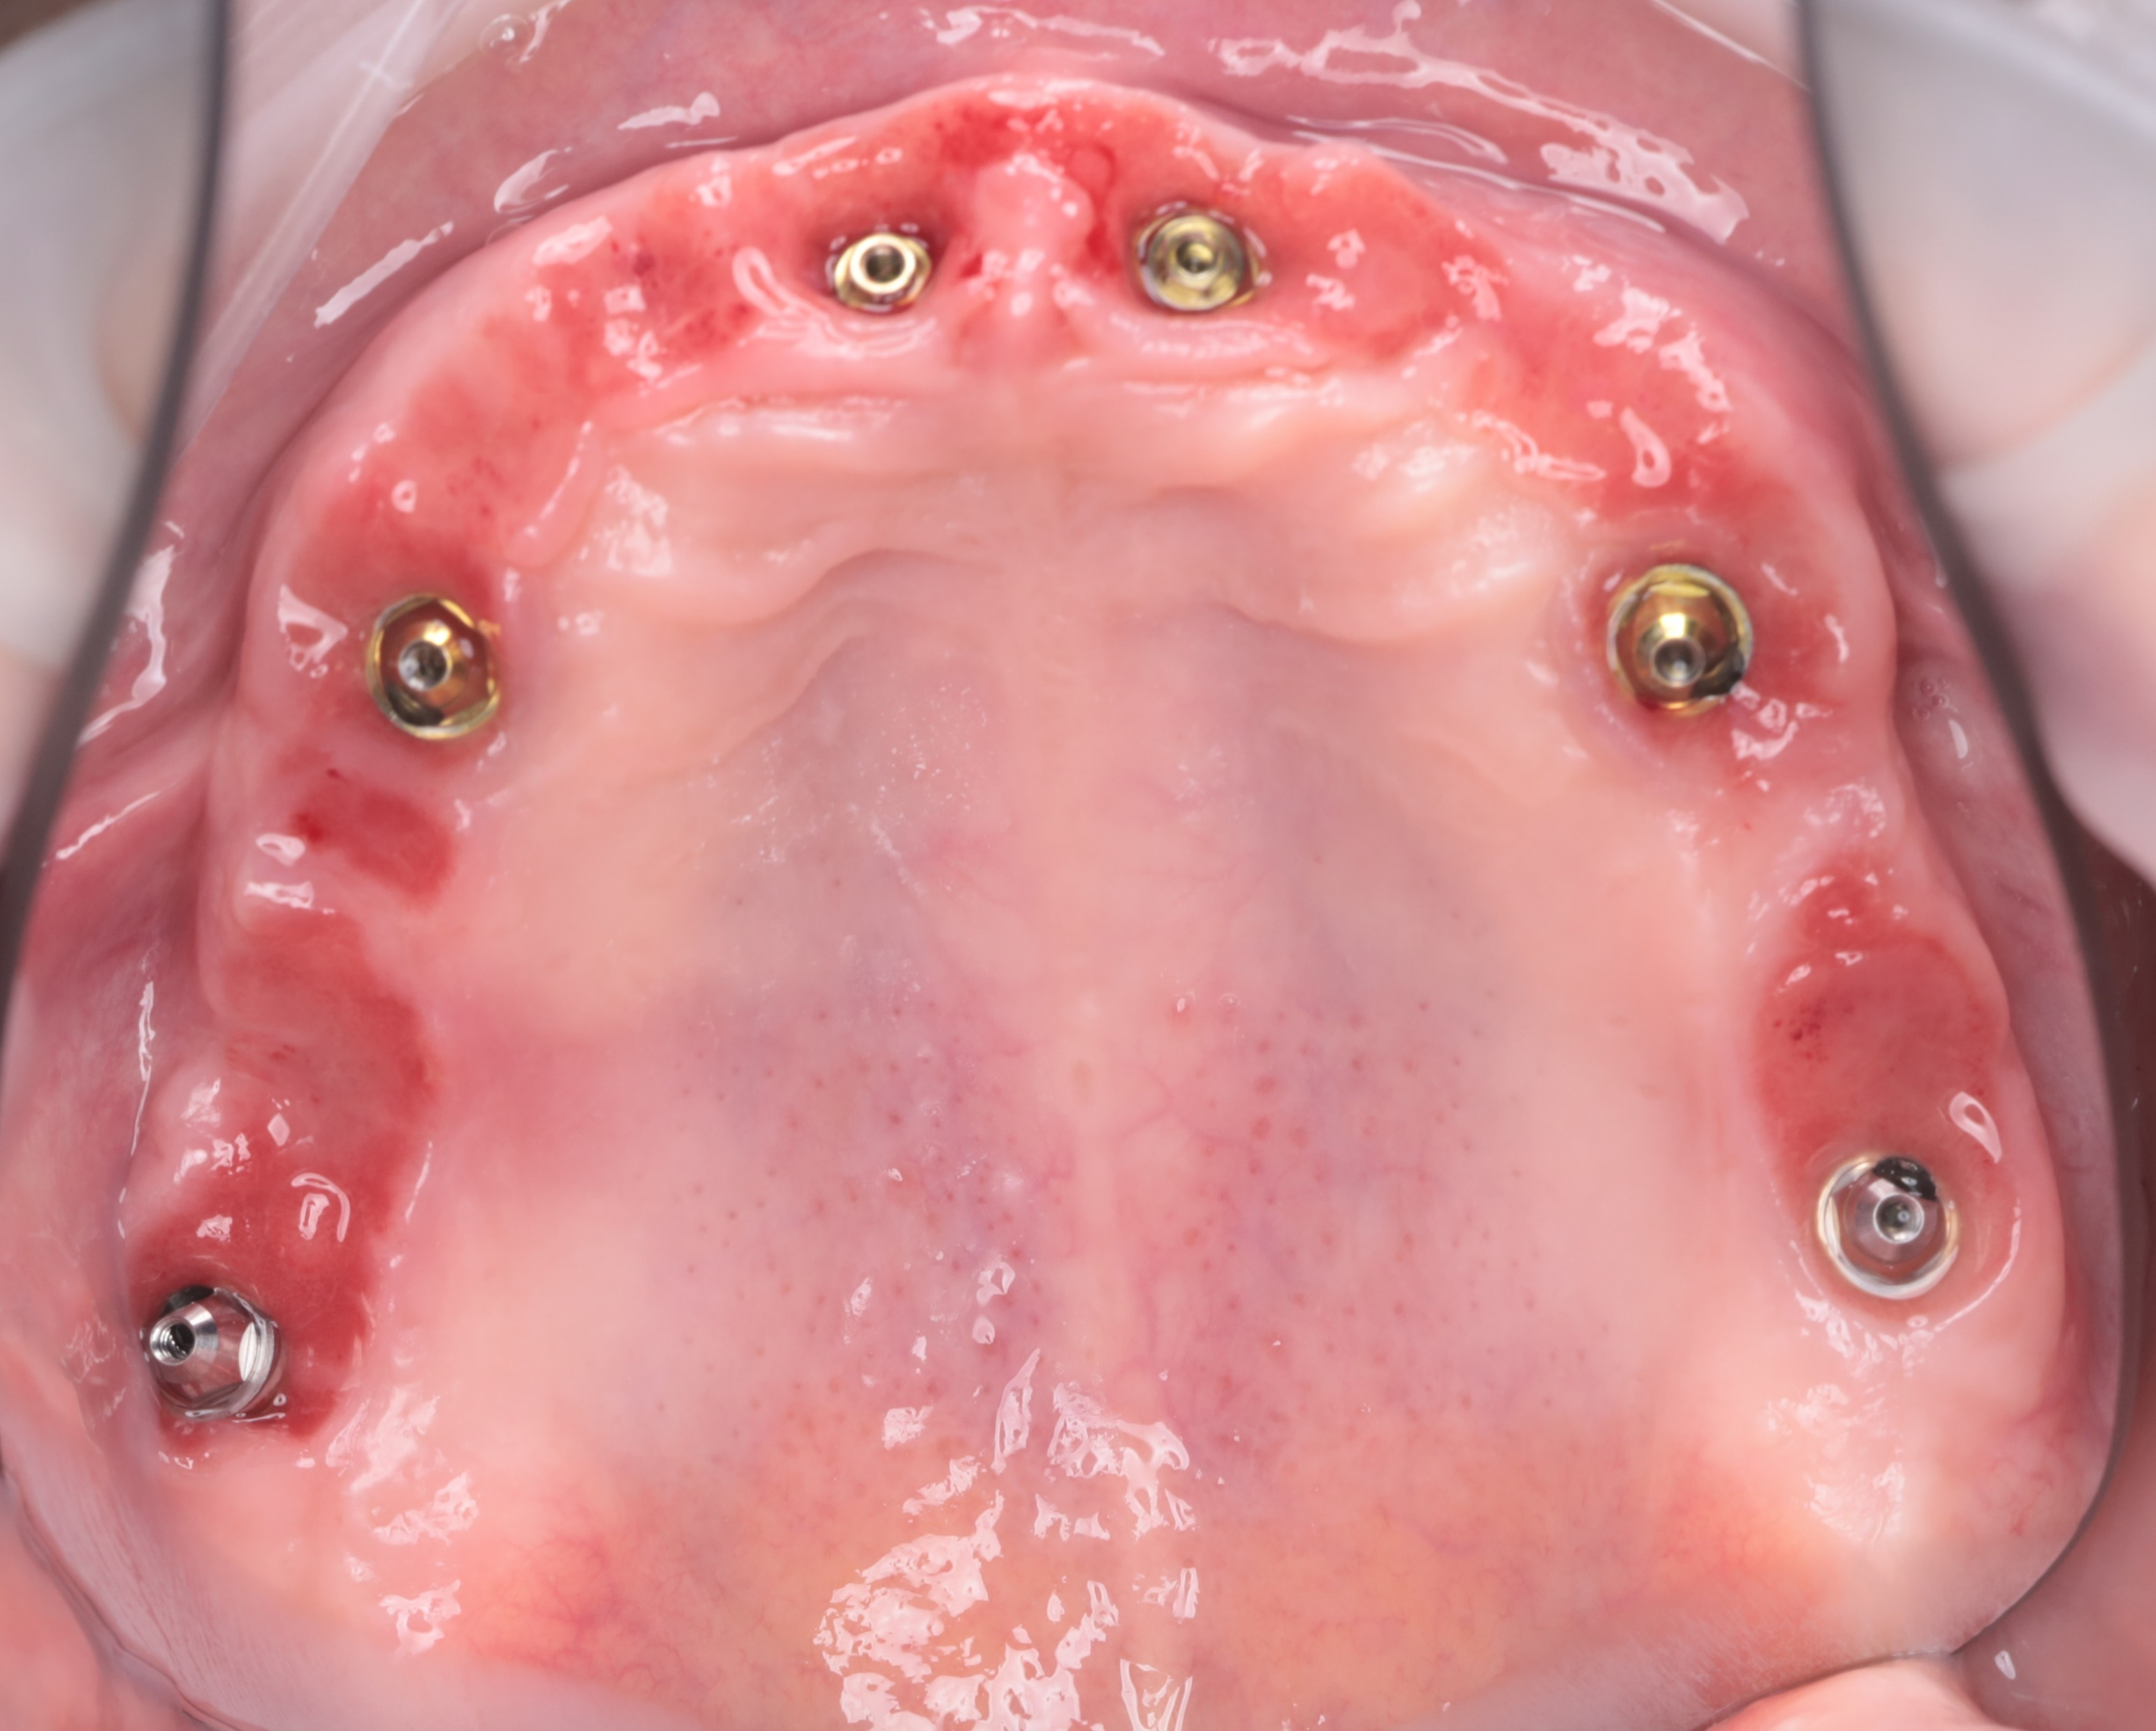

Six-Month Follow-Up

At the six-month follow-up, the patient reported high satisfaction with the functional and aesthetic performance of the provisional restorations. Clinical examination following the removal of the provisionals revealed optimal soft tissue healing and well-preserved gingival architecture. Notably, the Root Shield sites at 13, 12, and 23 successfully maintained the buccal ridge contour, while radiographic evaluation (OPTG) confirmed complete osseointegration of all implants, including the pterygoid fixtures at sites 17 and 27.